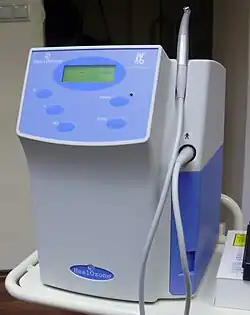

Le dentiste peut également utiliser un laser dentaire (sono-abrasion par ultra-sons) ou des instruments d'air abrasion par sablage (technique utilisée notamment pour traiter les lésions situées entre deux dents), si l'émail des dents à traiter n'est pas trop épais, si la carie est débutante[1], ainsi que des appareils à ozone dans le même cas de figure. L'intervention au laser est généralement plus coûteuse que l'intervention à la fraise.